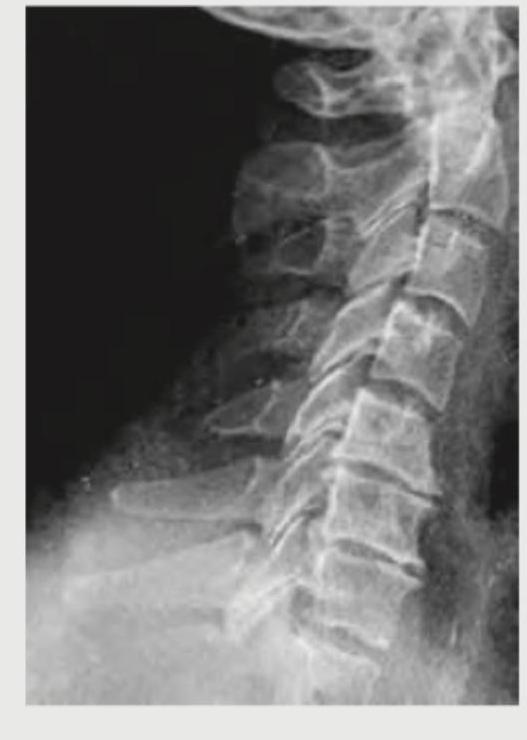

Question 2: A patient presents with neck pain and rigidity which gets relieved after bathing in hot water and exercise. Cervical X-ray is shown below. What is your diagnosis?

- C. Spondylitis (Correct Answer)

Explanation: ***Spondylitis (Ankylosing Spondylitis)*** - The image shows **fusion of vertebral bodies** (ankylosis) and an appearance consistent with a **bamboo spine**, which is characteristic of advanced **Ankylosing Spondylitis**. - The clinical presentation is pathognomonic: **inflammatory back pain with morning stiffness** that is **relieved by activity and hot water bathing** (as opposed to mechanical pain which worsens with activity). - This is a classic presentation of inflammatory spondyloarthropathy, specifically ankylosing spondylitis. *Spondylolisthesis* - This condition involves the **slippage of one vertebra over another**, which is not the primary finding on this X-ray. - While spondylolisthesis can cause neck pain, it does **not typically present with diffuse vertebral fusion** as seen here, and the pain would worsen with activity (mechanical pattern), not improve. *Spondylosis* - Spondylosis refers to **degenerative changes** of the spine, often involving **osteophytes** and **disc space narrowing**. - While some degenerative changes may be present, the pronounced fusion and **"bamboo spine" appearance** go beyond typical spondylosis and indicate an inflammatory process. - Degenerative pain typically **worsens with activity**, unlike the relief with exercise seen in this patient. *Spondyloptosis* - Spondyloptosis is an **extreme form of spondylolisthesis** where one vertebra has completely slipped off the one below it (Grade V slip). - This severe displacement is not apparent on the X-ray; instead, there is **fusion rather than translational instability**.